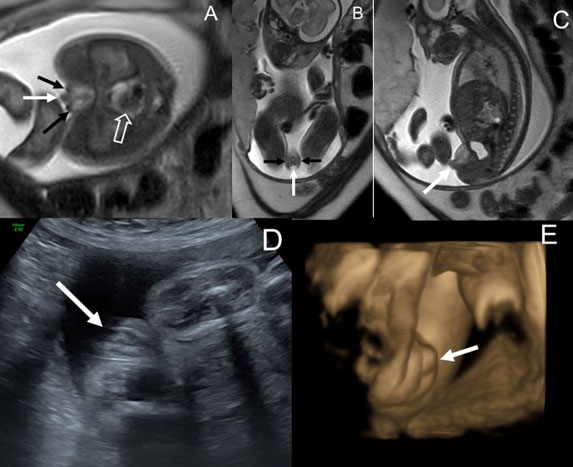

This was a female baby born to a 20-year-old mother G4P0030 referred to the CFCC for intrauterine growth restriction (IUGR) and ambiguous genitalia on US, noted to be a phallus with labioscrotal folds with no other anomalies noted. Fetal MRI demonstrated an abnormal appearance of the external genitalia characterized by morphologic labia majora and an intervening genital protuberance, possibly reflecting clitoromegaly/phallus. The uterus was visualized in the fetal pelvis, but no gonads were visible. There was also broadening of the column of bright T1-weighted meconium signal in the rectum, which in the setting of abnormal genitalia raised the suspicion for underlying anorectal malformation (Figure 1).

Figure 1: Axial and sagittal (A, B) T2 Single Shot Fast Spin Echo and axial (C) T2 Steady State Free Precession MR images of a 24 weeks 6 days female fetus showing ambiguous appearance of the external genitalia characterized by morphologic labia majora (black arrow in A) and an intervening genital protuberance (black arrow in B) that may reflect clitoromegaly/phallus. Normal urinary bladder (white arrowhead in C), uterus (open white arrow in C), and rectum (solid white arrow) are visualized within the pelvis (C). (D) shows the postnatal appearance of the external genitalia with double labia majora (white arrows), mons pubis protuberance (black arrow), and the additional finding of imperforated anus, not diagnosed in-utero.